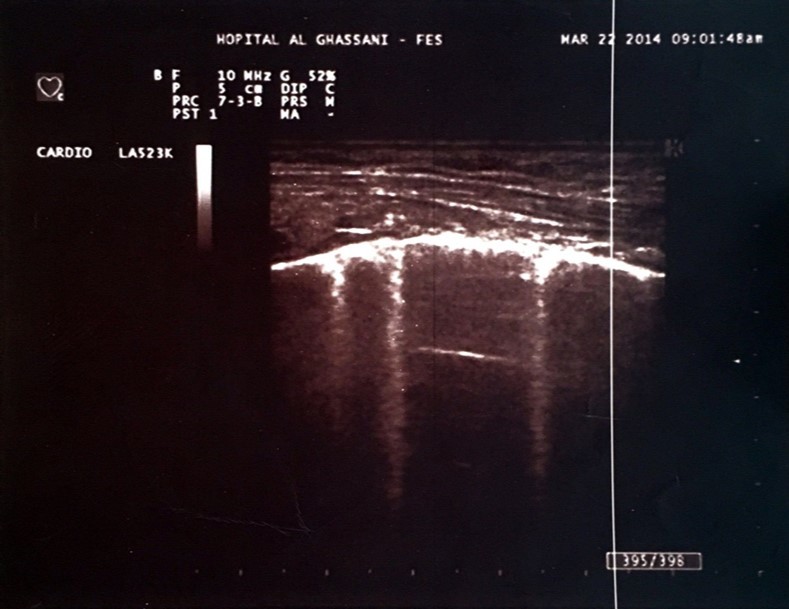

One of the most interesting tools is the use of the lung ultrasound to detect the presence of extravascular lung water (LW). In the presence of excessive LW, the US beam is reflected by subpleural thickened interlobular septa, a low impedance structure surrounded by air with a high acoustic mismatch. This US reflection generates hyperechoic reverberation artifacts between thickened septa and the overlying pleura that are known as “lung comets” or B-Lines 5. Lung comets are defined as vertical artifacts arising from the pleural line and extending to the edge of the screen that move synchronously with respiratory acts 6 (Figure 1).

Figure 1.Hyperechoic microreflections indicating the presence of extravascular lung water known as B-lines in one of our patients.

Hyperechoic microreflections indicating the presence of extravascular lung water known as B-lines in one of our patients.